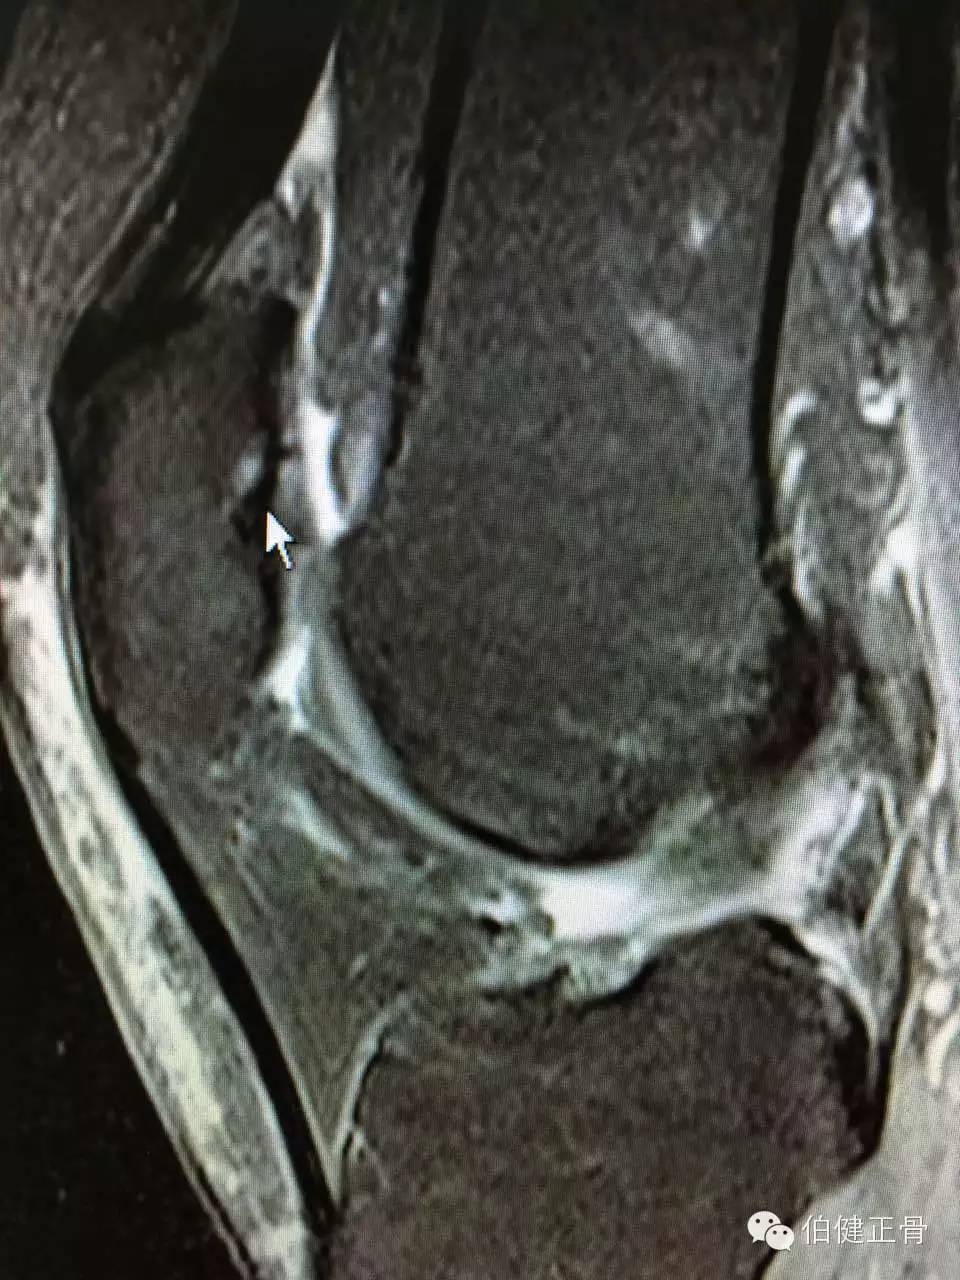

附髌骨软化症的诊断:

3.X线检查:照膝关节正,侧位及髌骨切线位X线片,早期无异常所见,晚期可因软骨大部磨损,髌骨与股骨髁部间隙变窄,髌骨和股骨髁部边缘可有骨质增生。

诊断髌骨软化症的主要依据是髌骨后的疼痛,髌骨压磨试验和单腿下蹲试验引起髌骨后疼痛,应该注意检查有无合并半月板损伤和骨关节炎等。